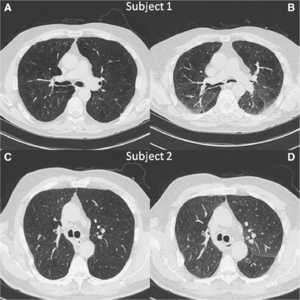

Publication: J Thorac Imaging. 2016 Jan;31(1):29-36. PMID: 26429588| PDF Authors: Zach JA, Williams A, Jou SS, Yagihashi K, Everett D, Hokanson JE, Stinson D, Lynch DA, COPDGene Investigators. Institution: Divisions of Radiology, Biostatistics and Bioinformatics, National Jewish Health, Denver, CO, USA. Background/Purpose: The purposes of this study were to evaluate the effect of smoking status on quantitative computed tomography CT measures of low-attenuation areas (LAAs) on inspiratory and expiratory CT and to provide a method of adjusting for this effect. Materials and Methods: A total of 6762 current and former smokers underwent spirometry and volumetric inspiratory and expiratory CT. Quantitative CT analysis was completed using open-source 3D Slicer software. Funding:

Examples of CN on CT. Coronal CT image of a GOLD 1 subject with moderately extensive visual extent of emphysema. However, the quantitative emphysema score was only 5.1%. The emphysema may have been masked on quantitative assessment by the presence of centrilobular nodules (circled) and patchy ground-glass abnormality (arrows). |